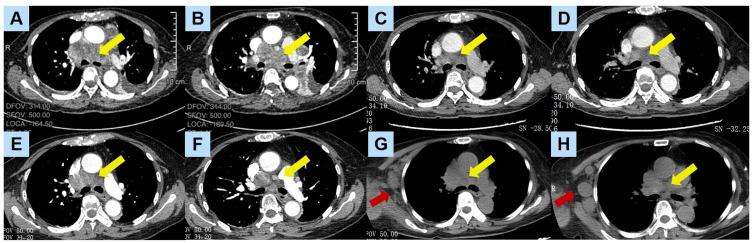

Epidermal growth factor receptor kinase domain duplication (EGFR-KDD) is a rare form of EGFR mutation. Unlike the classical mutations such as exon 19 deletion and exon 21 p.L858R point mutation, EGFR-KDD is a special type of large genomic rearrangement (LGR) that results in the duplication of the tyrosine kinase domain at the protein level, leading to the formation of an intramolecular dimer and activation of the EGFR signaling pathway. Case reports and in vitro experiments have shown that EGFR-KDD patients can benefit from EGFR TKI treatment. Similar to classical EGFR mutations, EGFR-KDD inevitably develops resistance during EGFR TKI treatment, leading to disease progression. Due to the rarity of EGFR-KDD, the acquired resistance mechanisms are not yet fully understood, but known mechanisms include EGFR amplification and T790M mutation. In this study, we report a 71-year-old female EGFR-KDD patient who showed a positive response to afatinib treatment initially, but developed resistance upon tumor progression. Subsequent next-generation sequencing (NGS) on the re-biopsy revealed TP53 exon c.688_764 deletion and MET exon 15-20 duplication, suggesting that MET bypass activation might be the acquired resistance mechanisms. Additionally, we conducted a literature review on EGFR-KDD and examined case reports of EGFR-KDD patients treated with EGFR TKIs to summarize the treatment outcomes and resistance mechanisms. We hope to provide more treatment information for patients with rare gene mutations in lung cancer.